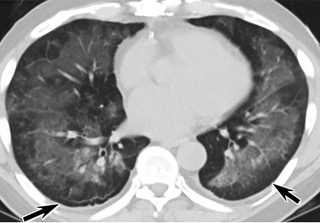

疑點二,中國科研工作者從60篇研究論文中篩選出142位電子煙肺炎患者的250張影像圖片,邀請3位放射科權威專家,對上述全部影像圖片、相關病人臨床信息以及文獻原文進行了仔細全面研究與審查,又有了新的發(fā)現(xiàn)。

16位被文獻報道為電子煙肺炎的患者被專家判定為“病毒性感染”,即有可能是新冠肺炎的“疑診患者”,其中更有5位臨床癥狀和治療情況相對完整的患者被判定為“中度可疑”。因此在2019年美國報道的電子煙肺炎中存在病毒性感染的病例,而且不排除美國電子煙肺炎中存在新冠肺炎的可能性。

疑點三,這16位患者均來自美國,其中4位患者的患病時間不詳,其余12位的發(fā)病時間均在2020年以前。針對美國早期新冠病例可能早于已知時間的報道和報告,美方始終沒有回應。